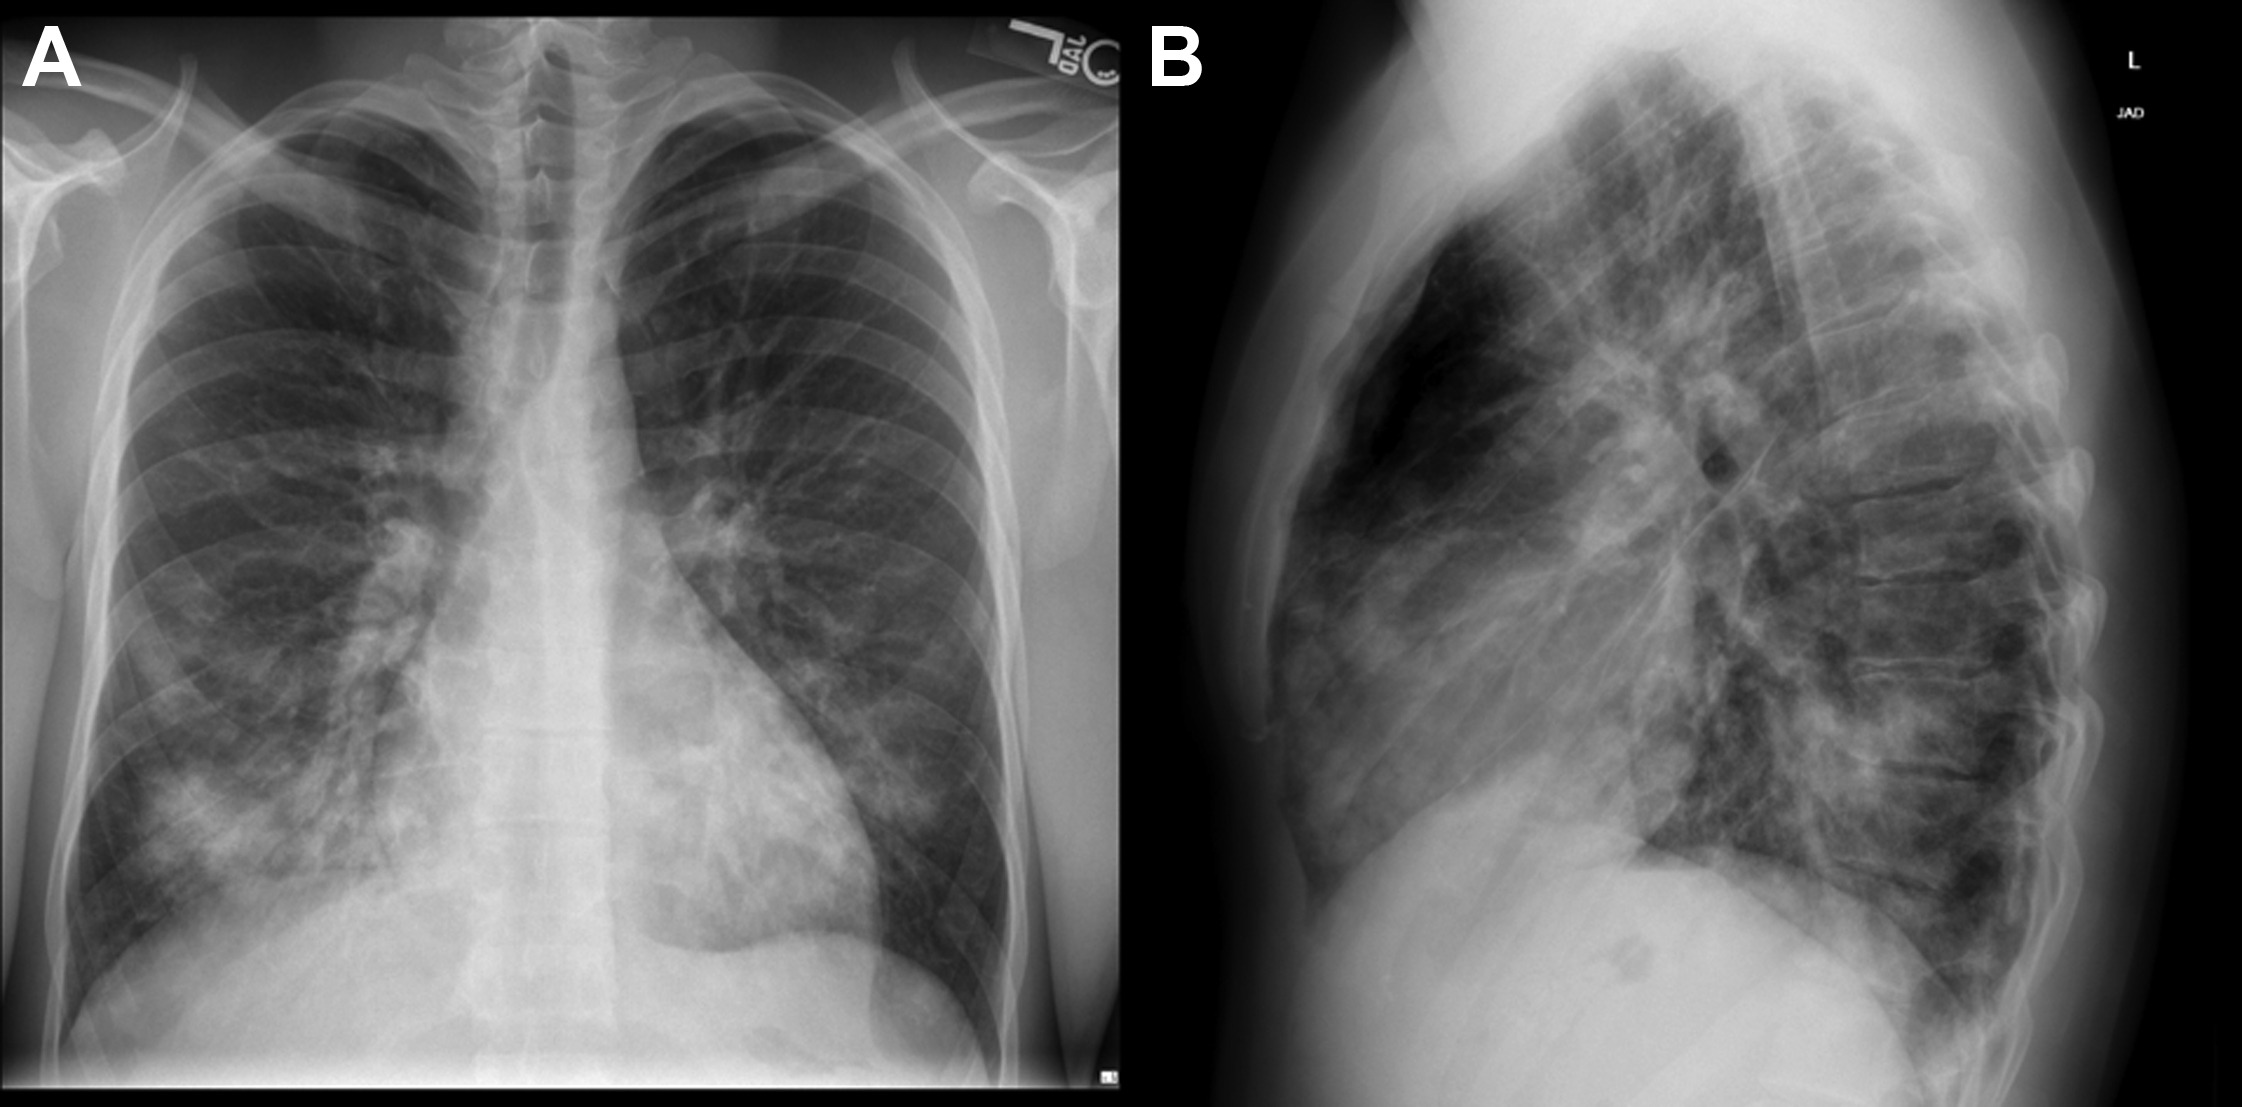

From www.cureus.com

Cureus SwimmingInduced Pulmonary Edema found in a U.S. Navy Basic Diving Pulmonary Edema Immersion pulmonary edema (ipe) is a rare condition that causes fluid to leak into the lungs of divers or swimmers. Immersion pulmonary edema is sudden development of fluid in the lungs that typically occurs early during a dive and at. Learn about the causes, symptoms, treatment and prevention of. Immersion pulmonary edema is a rare, underrecognized, and potentially lethal pathology. Diving Pulmonary Edema.